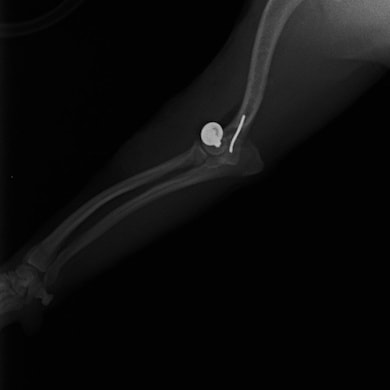

症例3:キルシュナーワイヤーのピンニングによる整復

ペルシャ猫 11ヶ月齢 雄

他院にて左大腿骨遠位の成長板骨折(salter-harrisⅠ型)が認められており、治療相談を目的として来院。当院にて、キルシュナーワイヤーを用いたピンニングにより骨折部位の整復を行いました。術後の経過は良好で、現在も経過観察中です。

術後レントゲン

Arthrex社のターゲティングデバイスを用いてピンニングの位置を調整することで、確実な固定を行っています。当院ではこの手術器具以外にも、人の手術にも使用される様々な器具を導入し、手術精度を高め、また医療メーカーと新しい器具の開発、試作にも取り組んでおります。